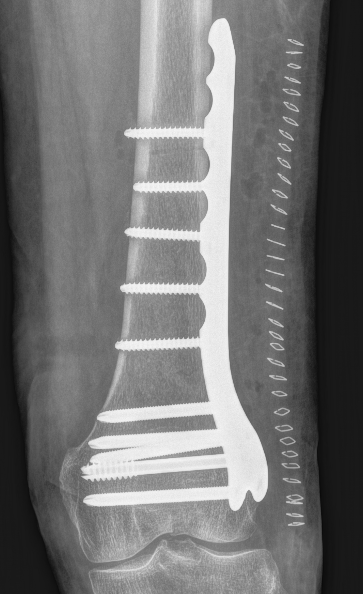

Lateral Plate

Surgical Technique

Approach

A. Lateral anterolateral approach

- longitudinal incision over lateral distal femoral condyle

- split ITB

- elevate vastus lateralis and cauterize perforators

B. Lateral parapatellar approach

Reduce intra-articular portion if required

- compress with bone reducing forcep

- cannulated screws

- anterior / posterior / distal to plate

Apply plate distally

- length, valgus alignment, rotation restored

- ensure screws not in joint / above blumensaat's

- ensure screws not in PFJ (distal femur is trapezoidal)

MIPO plate technique

- percutaneously elevate muscle off femur with elevator

- insert appropriate length plate (4 bicortical screws above)

- second proximal incision

- obtain indirect reduction

- attach plate with screws